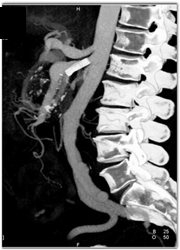

Neurogenic Tumor Simulates A Cystic Tumor